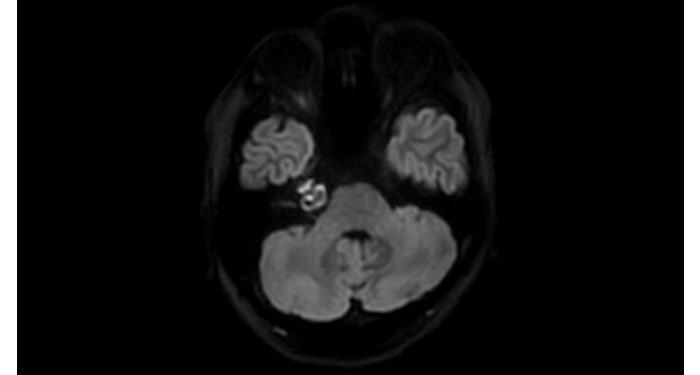

Hospital Eramse, Bélgica

Imágenes de la IRM de campos oscuros de un paciente con VIH con vasculitis cerebral

Las imágenes de campos oscuros ayudaron a sugerir el diagnóstico y elegir el tratamiento.